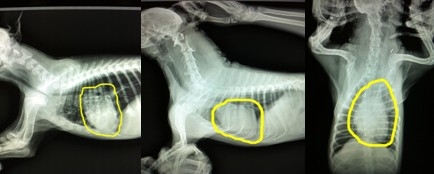

上圖中分享的依然是剛才的兩只犬的三張X光片,但是重點不一樣,通過圖片畫圈的位置可以發現,第一只犬是主要由于氣管狹窄,通氣不足引起的喘氣急促。第二張圖片,圖片中心臟的面積幾乎占了整個胸腔的一半,形狀也有明顯的異常,而氣管并沒有明顯異常影像,另外通過醫生的聽診和第三張不同體位的X光片的檢查分析,可確診此犬患有心臟病。X光片的確診對于心臟病十分重要,醫生會通過專業的測量和計算來判斷心臟病的類型和嚴重程度。

上面這兩張圖片來自于我院的兩張X光數碼片,第一張圖片是一根正常的氣管,第二張可以在尖頭所指的地方看見明顯的狹窄,由于此圖是手機翻拍,若為原圖,更加明顯,通過對比您可以清晰的發現區別和問題,所以及時就醫是非常積極的措施。